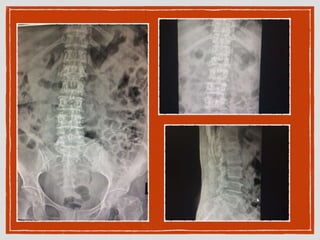

thoracolumbar spine : midline back pain level L1L2

A - alignment : 4 line ant/post. vertebral

body/lamina/spinous

no subluxation, no stepping, loss of kyphosis/lordosis

spondylolithisis,retrolithisis

B - bone : vertebral height, shape(square/wedge),

density(osteolytic, osteoblastic lesion), homogenous

end plate involve, subchondal sclerosis, marginal

osteophyte

C - cartilage : disc narrowing, vacuum disc, facet joint

D - distance : interpedicular distance (เพิ่มขึ้นจากบนลงล่าง ให้เทียบ

กับอันล่าง ถ้ากว้างกว่าแปลว่า+)

E - external soft tissue : paravertebral soft tissue, psoas

muscle

R/o compression fracture L1

A - alignment: 4 line ant/post. vertebral body/lamina/spinous no subluxation, no stepping, loss of kyphosis/lordosis spondylolithisis,retrolithisis B - bone : vertebral height, shape(square/wedge), density(osteolytic, osteoblastic lesion), homogenous end plate involve, subchondal sclerosis, marginal osteophyte C - cartilage : disc narrowing, vacuum disc, facet joint D - distance : interpedicular distance (เพิ่มขึ้นจากบนลงล่าง ให้เทียบ กับอันล่าง ถ้ากว้างกว่าแปลว่า+) E - external soft tissue : paravertebral soft tissue, psoas muscle